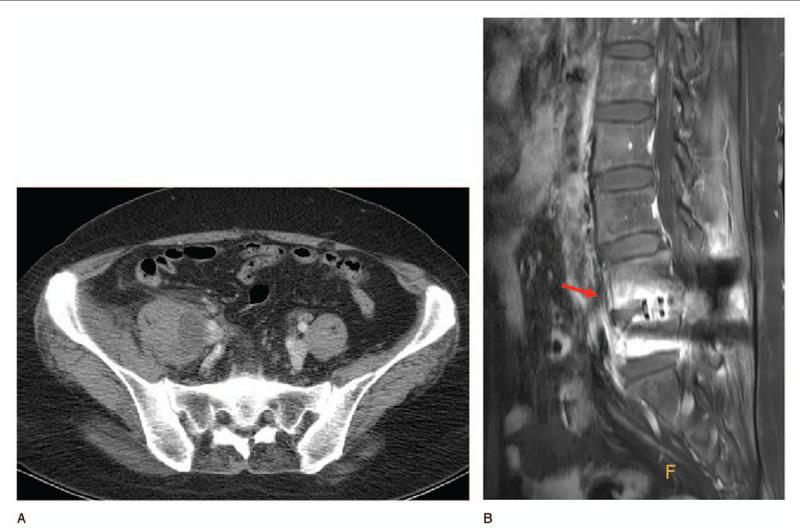

腰大肌脓肿是一种罕见但可能具有毁灭性的疾病,与神经功能缺损、感染性休克甚至死亡风险相关。目前的一线治疗方法是在影像引导下进行经皮导管引流(PCD),并联合使用广谱抗生素。如果PCD失败或无法进行,则应考虑手术引流。尽管已经出现了许多关于PCD和开放手术引流的研究,但腹腔镜引流的结果很少被报道。因此,我们对6例患者的腰大肌脓肿进行了腹腔镜引流;引流彻底,未出现复发或并发症。所有患者均通过X线平片、增强CT和实验室检查进行评估;所有患者均随访1年。当PCD失败时,腹腔镜引流是一种很好的治疗选择,具有开放手术的所有优点(彻底引流、切除感染组织以及同时治疗伴发病变)。此外,腹腔镜引流微创,切口小,恢复快。